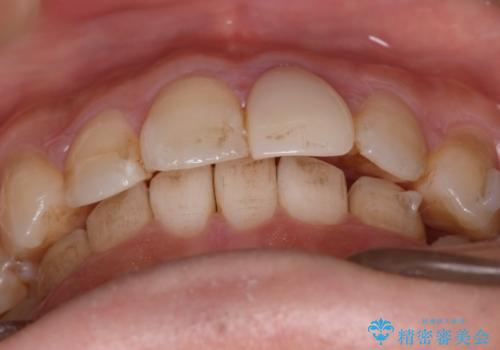

- 前歯のがたつきと口元を下げたいとのことで来院されました。

骨格的に左右差があるので正中を合わせることと抜歯矯正での口元改善は難しいことを説明させていただきました。

患者様に理解していただいた上で、インビザラインにてIPR(歯と歯の間を削る処置)を行いながら前歯のがたつきを整える治療計画を立てました。

インビザラインにて治療を行うことで、前歯のがたつきが改善されました。

左上1番目の前歯はセラミックをご希望されたので、セラミックにて被せ物の治療を行いました。

とても綺麗な前歯になりました。